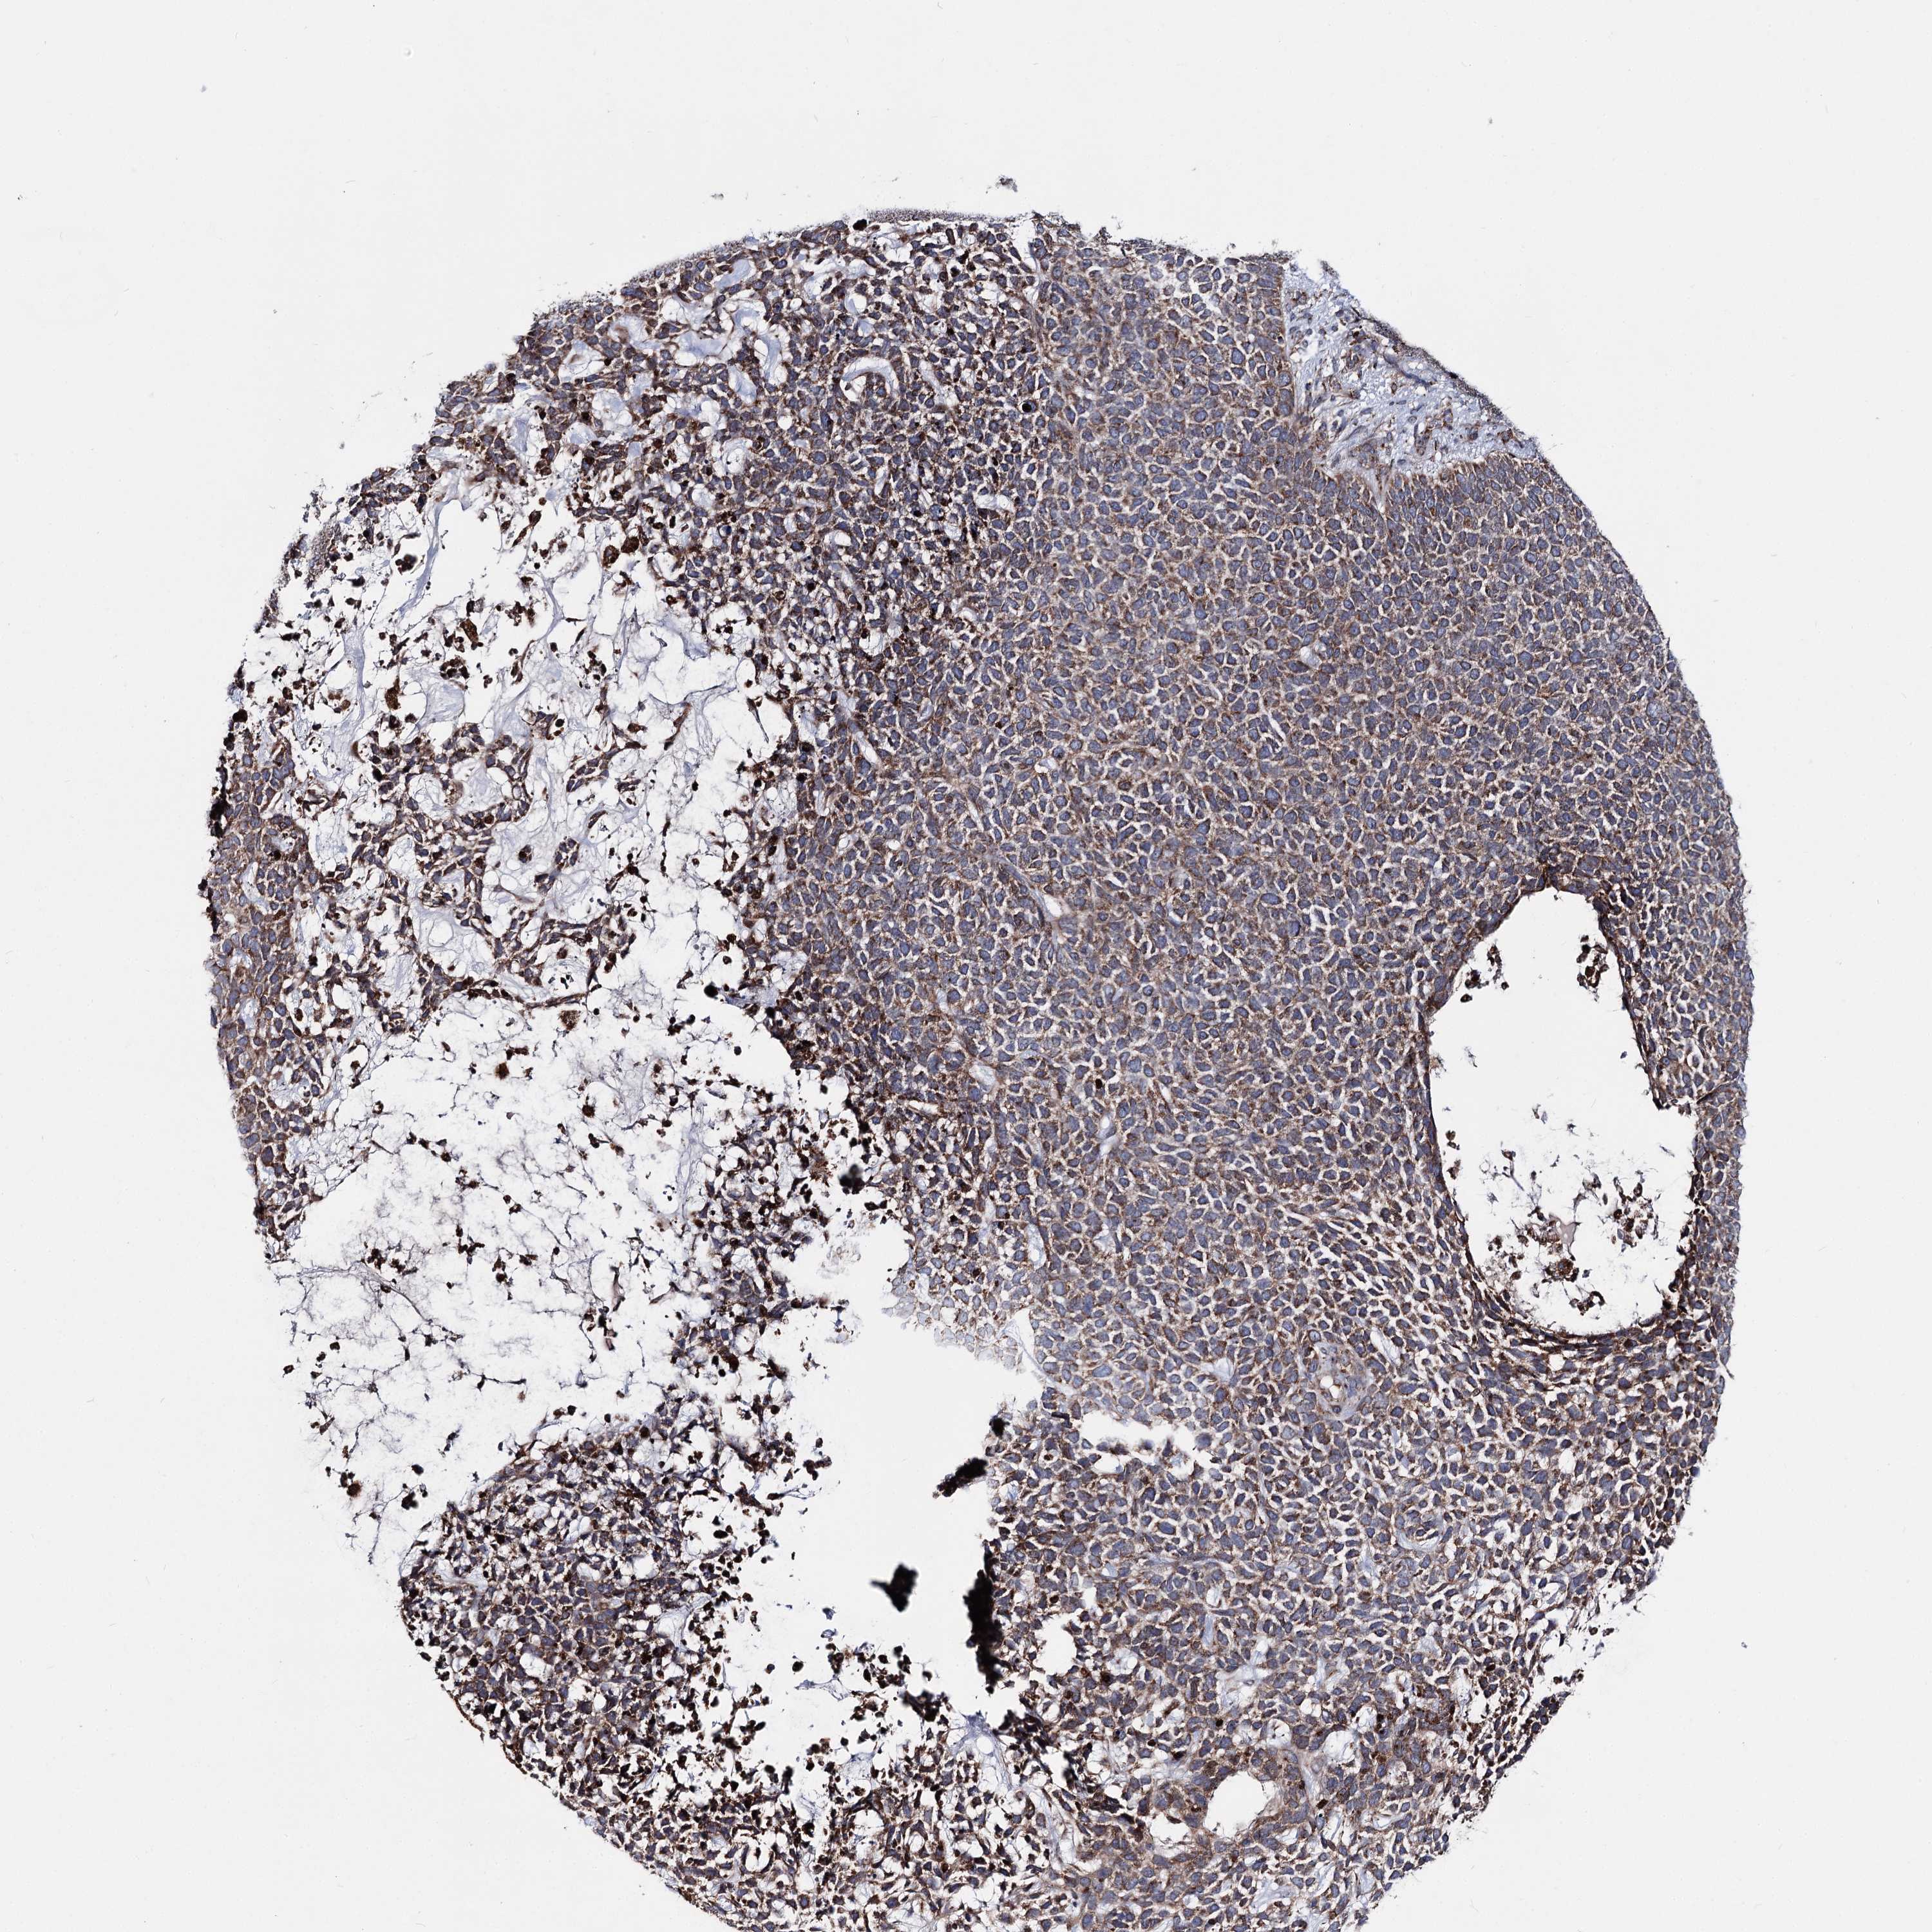

Basal cell and squamous cell cancer

SKIN CANCER - Protein expressioni

A mouse-over function shows sample information and annotation data. Click on an image to view it in a full screen mode. Samples can be filtered based on level of antibody staining by selecting one or several of the following categories: high, medium, low and not detected. The assay and annotation is described here.

Each image is clickable and will lead to virtual microscopy that enables deeper exploration of all samples and also displays staining intensity scores, fraction scores and subcellular localization as well as patient and tissue information for each sample.

Antibody HPA038694

Antibody HPA038695

Basal cell carcinoma